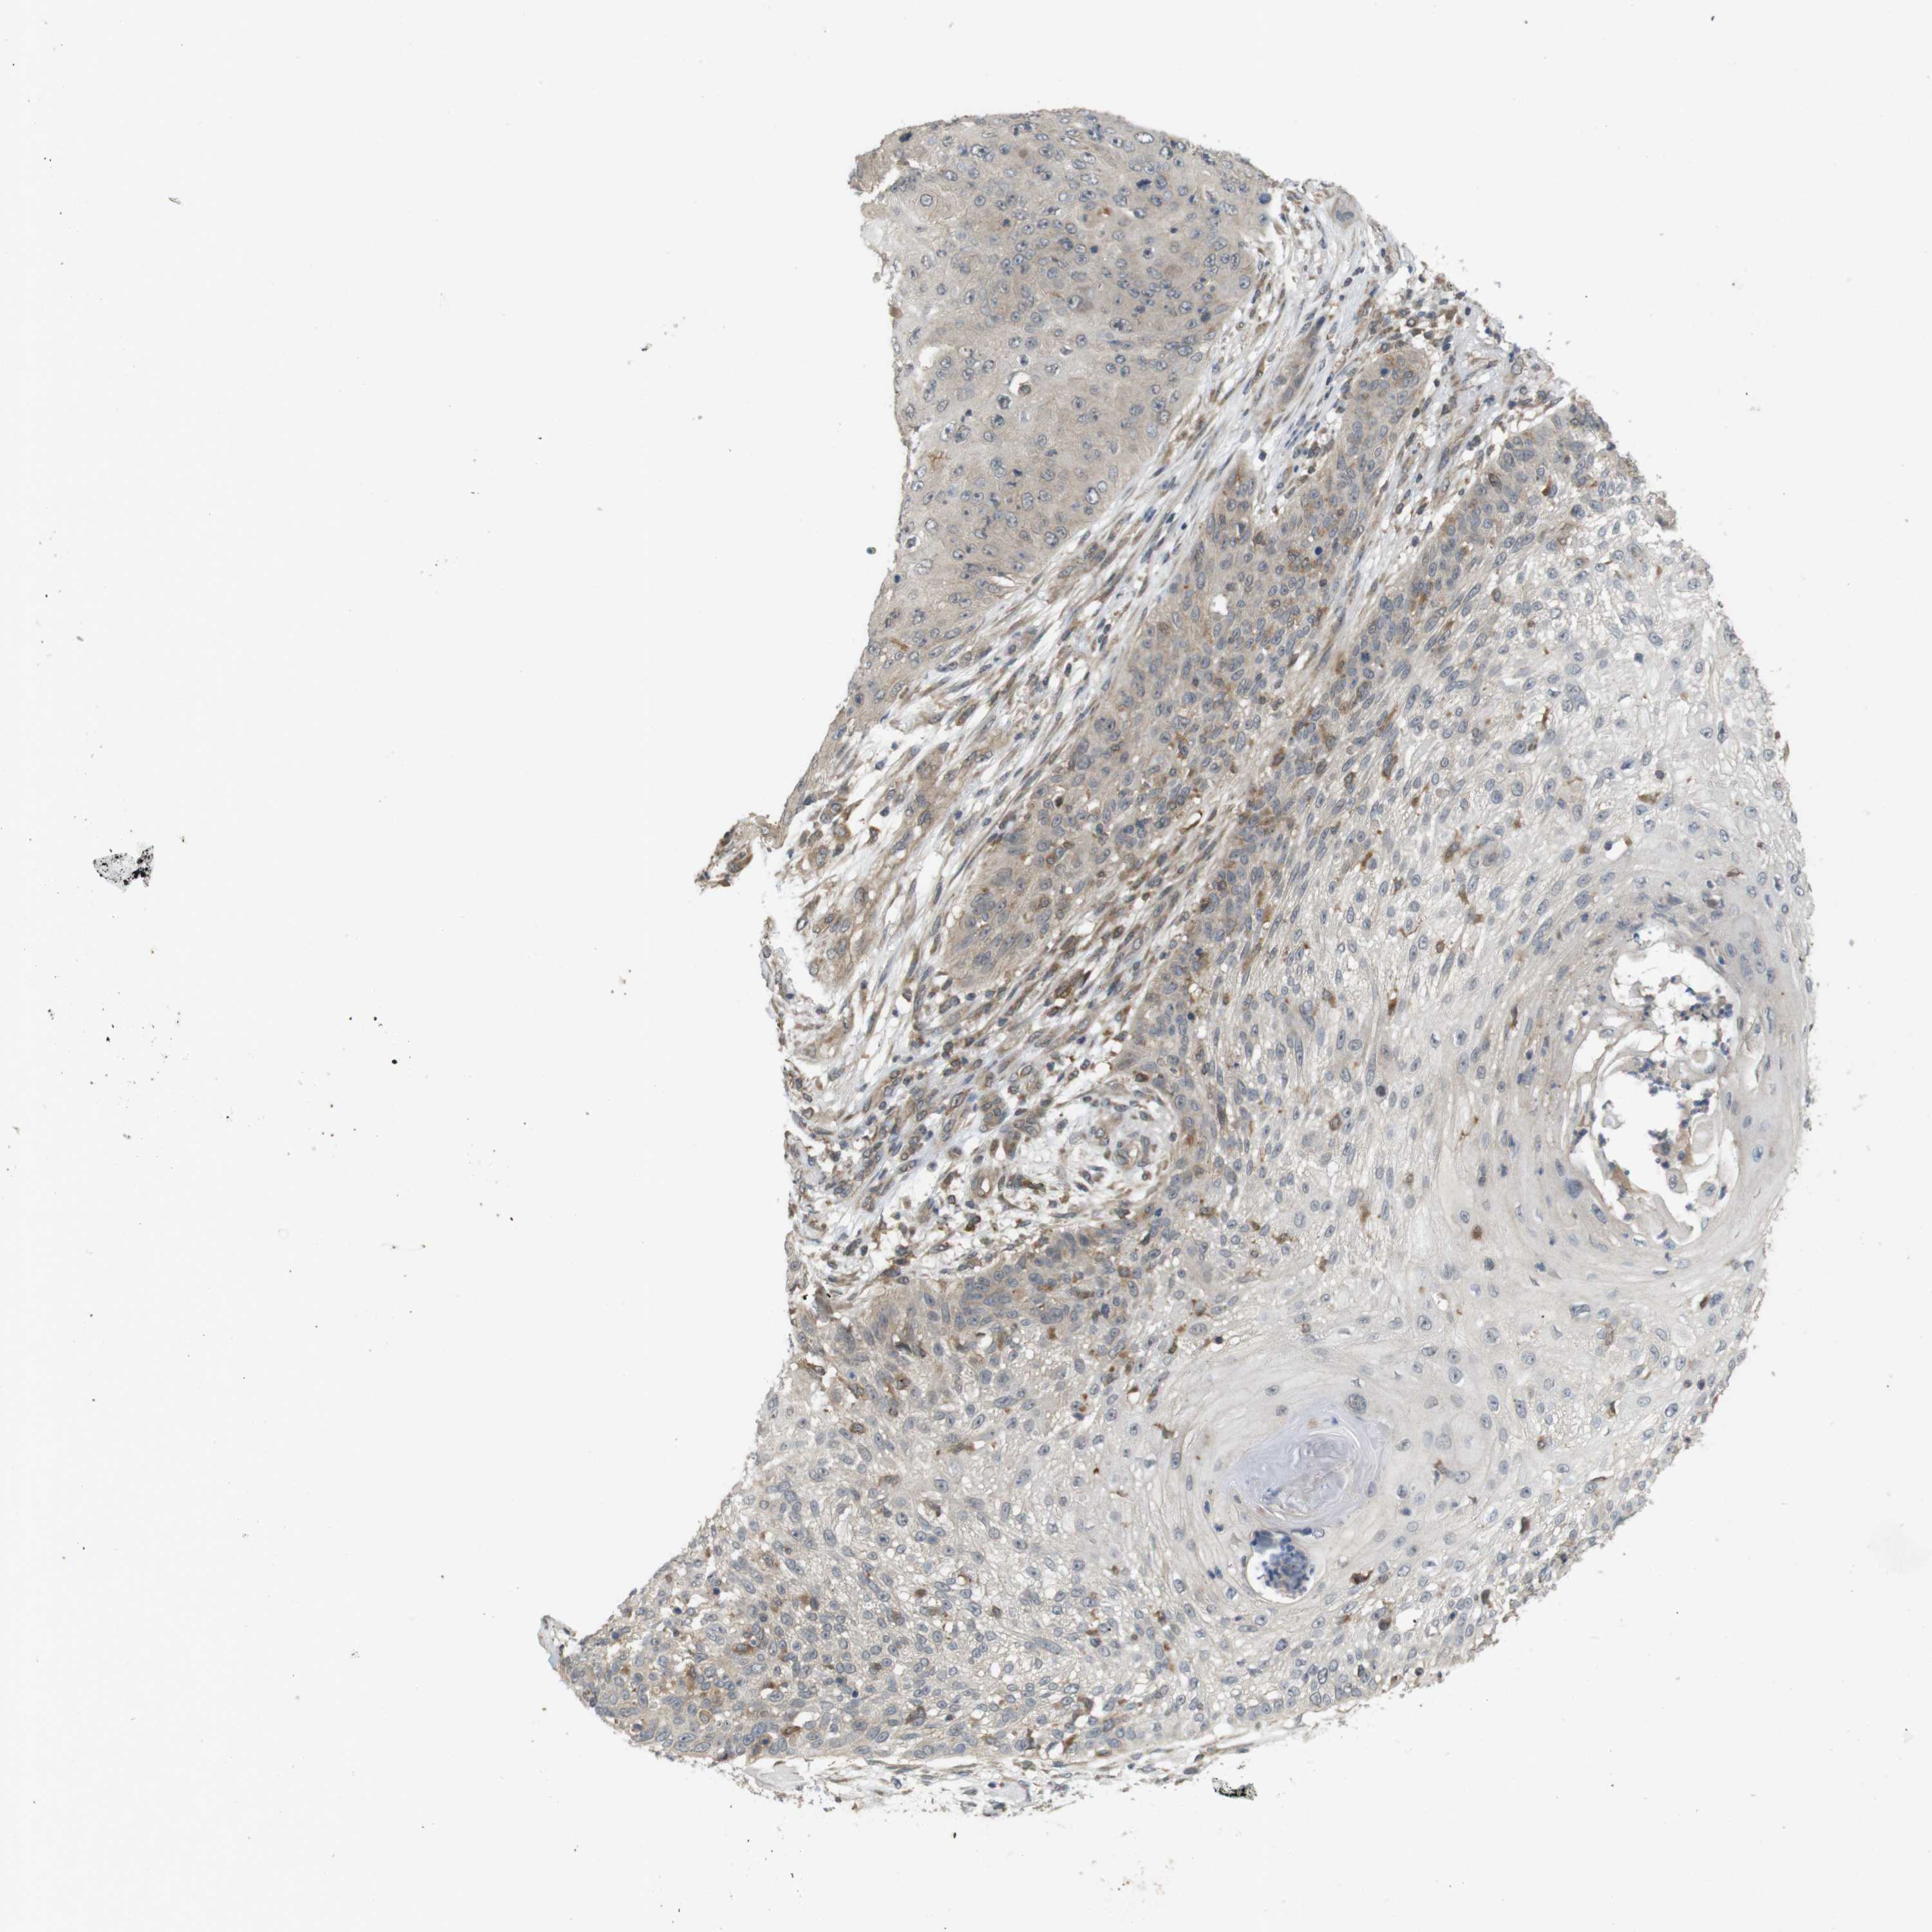

SKIN CANCER

Basal cell and squamous cell cancer